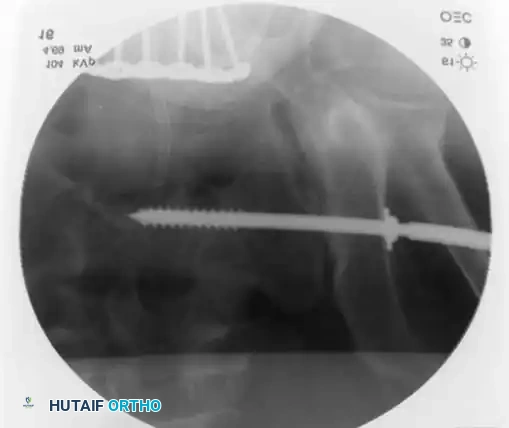

3. Percutaneous Sacroiliac (SI) Screws (Posterior Ring)

The gold standard for posterior ring fixation in appropriately selected patients.

* Indications: Sacral fractures, SI joint disruptions, crescent fractures.

* Technique: Performed under strict fluoroscopic guidance (Inlet, Outlet, and Lateral sacral views).

* Trajectory: The guide wire is advanced from the lateral ilium, across the SI joint, into the S1 (or S2) vertebral body.

* Safety Corridors: The surgeon must possess an intimate understanding of sacral dysmorphism. The "safe zone" is bounded by the sacral neural foramina inferiorly, the spinal canal posteriorly, and the sacral ala anteriorly.

Pitfall: Failure to recognize a dysmorphic sacrum (characterized by upper sacral segment elevation, non-recessed alae, and oblique neural foramina) can lead to catastrophic L5 nerve root injury or vascular penetration during SI screw placement.